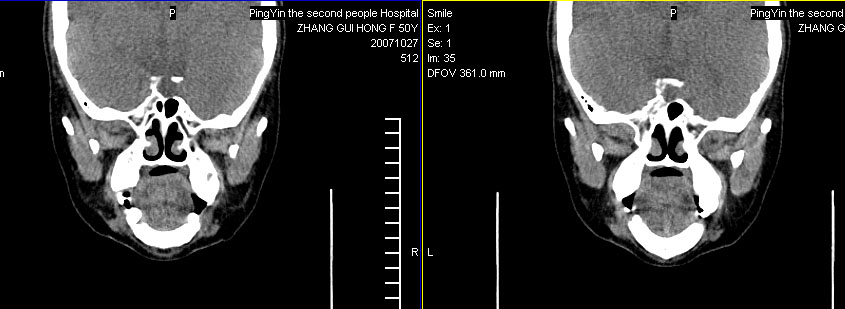

标题: CT10219:蝶鞍区有无异常?

女。50岁.头疼恶心半月余.双上颌窦区压疼明显,曾有高血压.现基本控制.

有问题,双侧侧脑室扩大,感觉鞍区有肿块,建议增强扫描.

感觉鞍区异常,建议增强扫描.